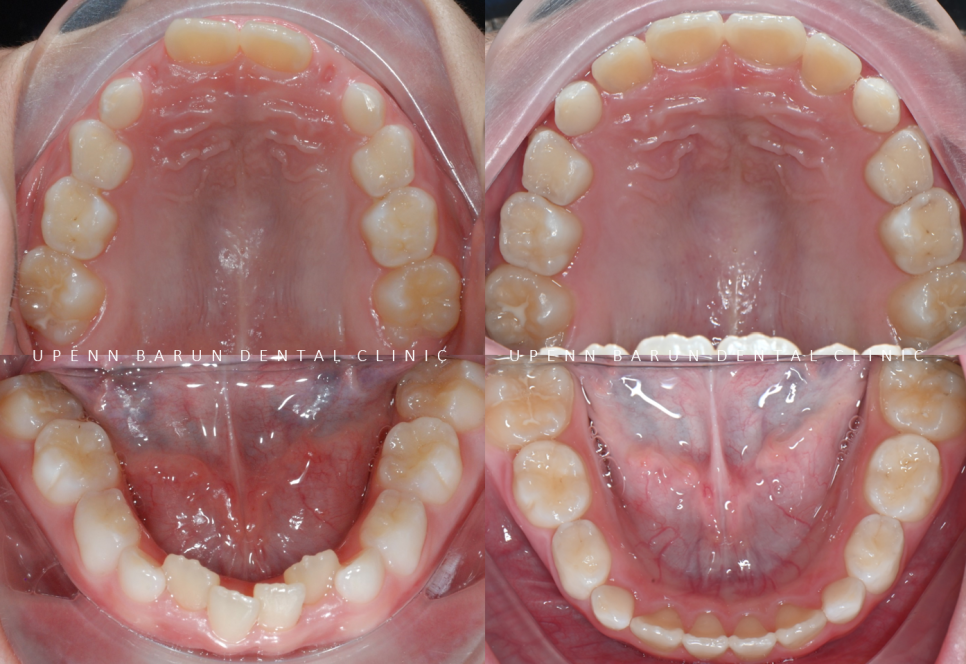

교정기간 23/8~24/7

잠실소아교정전문치과

잠실인비절라인전문치과

유펜바른치과 에서

인비절라인 퍼스트를 통해

11개월 만에 소아교정을 마무리 해드렸습니다 :)